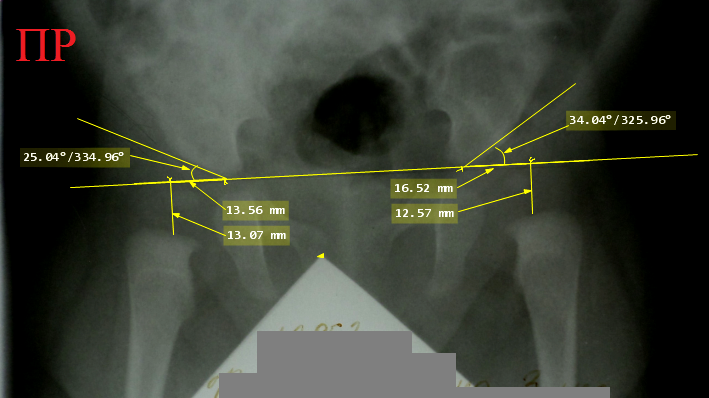

Снимок

тазобедренных суставов ребенка 3 месяцев с левосторонней дисплазией тазобедренного

сустава. Ацетабулярный угол слева превышает норму, там же имеет место очевидное

преобладание горизонтальной позиции над вертикальной. Если присмотреться, то

можно заметить формирующиеся ядра окостенения головок бедренных костей и то,

что слева ядро определенно меньше по размеру.